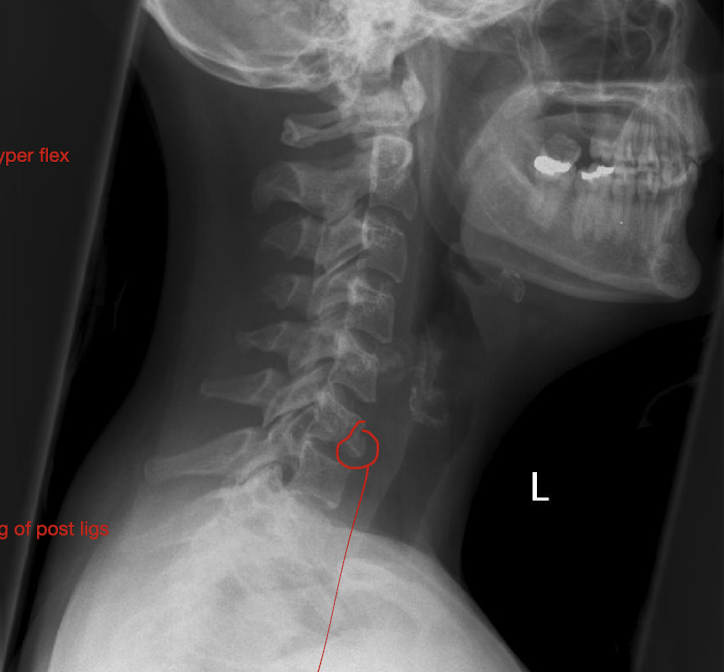

Fracture of C3-C7: Tear Drop Fx

What is this fx known as?

How does it occur?

2

Known as:

Most severe of the Lower C/S Fx (Hyper Flexion)

How:

Separation of a piece of bone from the Anterioinferior border of the vertebral border

Hyperflexion or Hyperextension

Fracture of C3-C7: Tear Drop Fx

How much force causes pieces to rupture off and tearing of post ligs.

Stable or Unstable Injury

Large Force

Unstabble